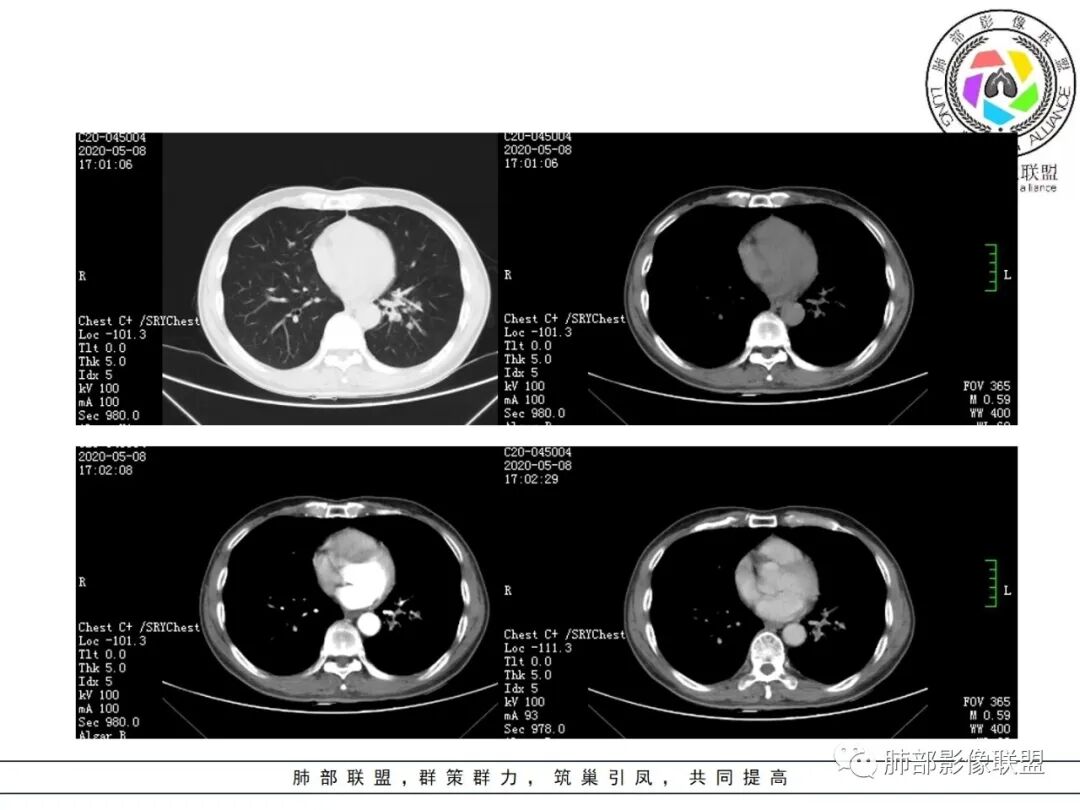

大雄:抗感染不吸收还是要警惕癌尤其主动脉旁的病灶红星:老年患者,咳嗽咳痰两个月,既往有糖尿病病史10年,左肺下叶后基底段斑片状、条索状、斑点状多形态的病灶,病灶内可见支气管征以及狭窄扩张的支气管影像。重建图像上可见到病灶沿支气管爬行。增强扫描病灶轻度强化,临近胸膜增厚。首先考虑感染性的病变,结核性的可能性最大。鉴别诊断上注意排除肺克以及淋巴瘤。三个石头:左肺下叶多发斑片,结节,条索,多态性?结核?多个结节边缘长毛刺,胸膜牵拉,分叶。矢状位支气管走行扭曲,没有完全阻塞,应该有粘液栓,有点像指状。主动脉旁病灶边缘平直,部分有鹏隆感,延迟强化。抗炎病灶变化不明显,结核?真菌?肿瘤也除外不了。没意见:左肺下叶基底段结节,膨隆、深分叶,毛刺,内侧串珠结节,中轴间质增厚,管腔狭窄,后基底段亚支不张,强化情况不明,考虑恶性,腺癌可能性大,另指套样征像,支气管壁增厚,不除外霉菌感染流心明智:老年患者,咳嗽咳痰2月。既往糖尿病史10年。胸CT:左肺下叶基底段多发结节影、斑片影、条索影,多数结节影沿支气管血管束分布,支气管壁厚,部分结节分叶、指状突,后基底段支气管狭窄闭塞。重建可见到病灶沿支气管爬行。增强扫描病灶明显强化,部分斑片影内可见低密度灶。普通抗感染无效。考虑:恶性病变,鳞?小?鉴别TB、隐球等。王秀仙:左肺下叶沿支气管血管束分布斑片、结节影,部分呈管状铸型生长,管腔狭窄,后基底段支气管阻塞,降主动脉旁不张实变,增强扫描病灶轻度强化,抗感染2周无吸收,考虑鳞癌。鉴别结核。蓝天白云:肺野内老年男性,咳嗽咳痰,有糖尿病病史,抗炎治疗无吸收。影像表现为左肺下叶支气管腔内结节影,支气管壁增厚,远侧小花小草,增强后实变影均匀强化,考虑鳞癌伴远端阻塞性炎症,鉴别结核。采莲:老年男性,咳嗽咳痰2月,有糖尿病史,左肺下叶沿支气管分布多发结节条状影,结节影不规则有分叶,成串珠样,靠下结节影成条索影,周围有空气储留,靠近主动脉不规则块状影,边缘平直,周围支气管壁增厚,支气管进入后阻塞,有糖尿病史,首选考虑炎性肺结核可能性大,鉴别肺鳞癌。了:左肺多发结节影,实性结节,,磨玻璃结节,左肺门结节影,深分叶,彭隆感,有血管滋养,考虑肿瘤,抗感染后病灶无吸收,感染不像,结节有强化,无卫星灶,结核可以排除不再涩的柠檬:老年男性,吸烟史,糖尿病史,咳嗽咳痰2月,抗感染2周无效。左下基底干及各分支管壁较弥漫增厚,伴支气管粘液栓,远端阻塞性肺炎,后基底段部分不张实变。先考虑感染病变,常规抗炎无效,需考虑结核、曲霉等,不能排除鳞癌合并感染,建议支气管镜检查。

尘缘:支气管壁增厚,沿支气管分布斑片状影,中远端支气管似堵塞,远端阻塞性改变,需要鉴别结核与肺癌,临床简单,镜检就行了。读片个人倾向于鳞癌伴感染吧。田园晚风:老年男性,有糖尿病史,咳嗽咳痰2月,左肺下叶沿支气管分布多发结节条状影,部分有分叶,成串珠样,靠下结节影成条索影,周围有空气储留,靠近主动脉不规则块状影,边缘平直,周围支气管壁增厚,支气管进入后阻塞,首选考虑肺癌可能性大,鉴别肺结核。

临床资料:老年男性,咳嗽咳痰2月余,慢性病史。有吸烟史40年(现已戒烟),抗感染治疗2周肺部病灶未见吸收。

影像所见:

肺气肿背景。

结节伴分叶。

斑片影,考虑阻塞性炎症。

支气管壁厚,支气管腔内高密度影填充。

周围散在斑片影及结节影,类似“小花花草草”的感觉。

2.关于支气管:上述病灶辖区外侧段支气管截断,环壁结节,远端阻塞性肺炎,是肺癌的重要征象。